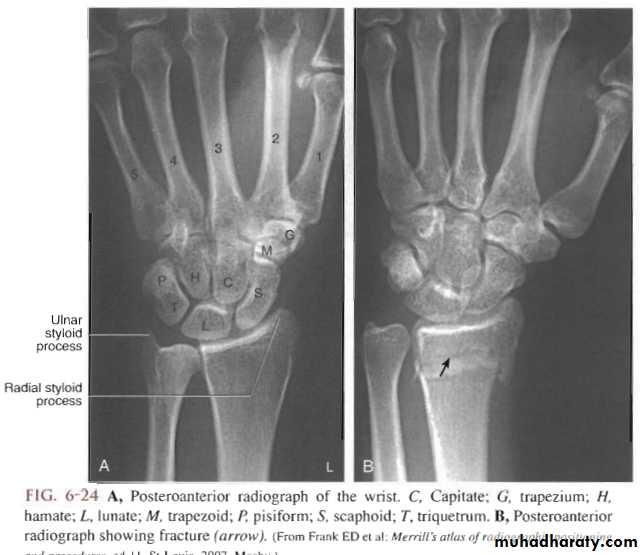

Radiological evaluation

Upper limbs

Lateral radiograph